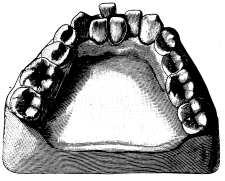

The Temporary Teeth.—For the removal of upper incisors and canines, a small pair of straight forceps of the pattern shown in fig. 34 should be used. The first upper temporary molars are best removed with a pair of forceps like fig. 35.

The lower incisors and canines require a small pair of hawk’s-bill forceps similar to the shape shown in fig. 27. For the lower temporary molars,{44} a small pair of forceps similar to that illustrated in fig. 29 should be used.

Fig. 34.   Fig. 35.

In removing the temporary teeth, care must be taken not to drive the forceps up too high, for fear of injuring the permanent teeth; this is more especially to be noted in connection with the temporary molars, as the roots of these teeth practically embrace the crowns of the bicuspids.{45} Generally speaking, if a temporary molar fractures in the attempt to remove it, the portion of tooth remaining in the jaw should be left alone unless it can be brought away quite easily.